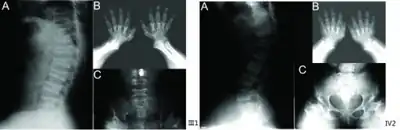

a) Anterior beaking of vertebral bodies b) short metacarpals and phalanges, cone-shaped epiphyses c) scoliosis, small femoral heads, flared metaphyseal borders

Skeletal radiography

Accurate assessment of plain radiographic findings remains an important contributor to diagnosis of pseudoachondroplasia. It is noteworthy that vertebral radiographic abnormalities tend to resolve over time. Epiphyseal abnormalities tend to run a progressive course. Patients usually suffer early-onset arthritis of hips and knees. Many unique skeletal radiographic abnormalities of patients with pseudoachondroplasia have been reported in the literature.[2][7][4]

- Together with rhizomelic limb shortening, the presence of epiphyseal-metaphyseal changes of the long bones is a distinctive radiologic feature of pseudoachondroplasia.

- Hypoplastic capital femoral epiphyses, broad short femoral necks, coxa vara, horizontality of acetabular roof and delayed eruption of secondary ossification center of os pubis and greater trochanter.

- Dysplastic/hypoplastic epiphyses especially of shoulders and around the knees.

- Metaphyseal broadening, irregularity and metaphyseal line of ossification. These abnormalities that are typically encountered in proximal humerus and around the knees are collectively known as “rachitic-like changes”.

- Radiographic lesions of the appendicular skeleton are typically bilateral and symmetric.

- Oval shaped vertebrae with anterior beak originating and platyspondyly demonstrated on lateral radiographs of the spine.

- Normal widening of the interpedicular distances caudally demonstrated on anteroposterior radiographs of the dorsolumbar region. This is an important differentiating feature between pseudoachondroplasia and achondroplasia.

- Odontoid hypoplasia may occur resulting in cervical instability.